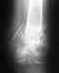

увеличенное место снимка перелома от 25.08.11